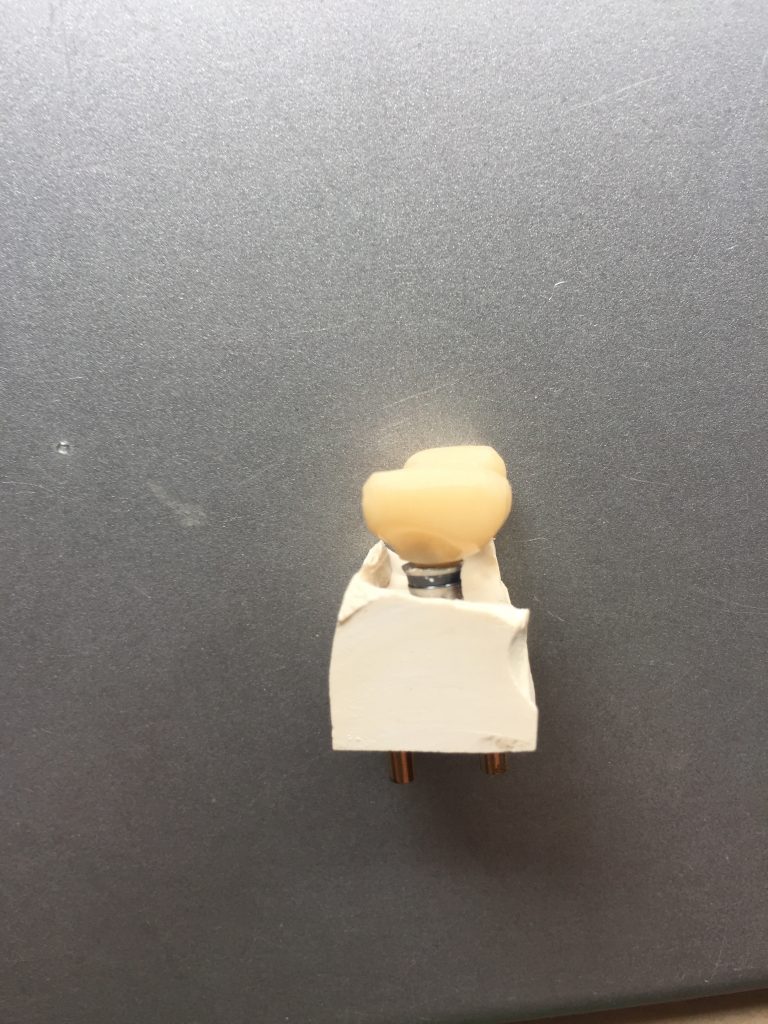

Autores: PRÓLOGO Asimismo, desde el punto de vista pedagógico, el profesional nobel en la materia tiene a su alcance la posibilidad de corregir cualquier posición implantaría en el ordenador, planear los provisionales y plasmarlos en la bio réplica antes de tocar al paciente a operar. Todos estos razonamientos nos llevan a presentar un caso de condiciones muy favorables para poner en práctica estos métodos como primer acercamiento a una Odontología Digital de alta calidad, con medios informáticos, que ya están presentes en la profesión de hoy en día, y será la protagonista única del futuro. Por otro lado, después de numerosos estudios que nos llevan a plantear el “gap” entre implante y pilar(abuttment), como principal responsable de la periimplantitis dado que la microbiota presente en el mismo es imposible de limpiar y en su presencia la cortical ósea reacciona reabsorbiéndose, nos ha llevado a utilizar implantes monobloc ya que los ejes implantarios y protéticos coincidían, y nos permitían su uso. Además, el circonio, ha mostrado a la luz de estudios muy recientes, una preservación y adhesión de los tejidos blandos superiores al titanio, tanto en su tratamiento de superficie de la rosca como a nivel gingival. DESARROLLO Paciente varón de 68 años, con antecedentes de radio/quimioterapia cinco años antes, con Rehabilitación Oral de los cuatro cuadrantes, con una Oclusión Mutuamente Compartida conservada, (REF.8) la que fracasa en el cuadrante 4, 19 años después. El mismo presentaba un puente de porcelana sobre circonio con pilares en 44 y 47, reemplazando el edentulismo de 45 y 46. Se produce la fractura del PM del 44, y ante una endodoncia antigua y corta, se decide implantar las zonas edéntulas, conservando temporariamente los pilares, hasta producida la oseointegración, para entonces también exodonciar el 44. DIAGNÓSTICO Tomamos impresiones del maxilar antagonista, Arco Facial Estático y realizamos montaje del mismo mediante la sistemática ARTEX. Producimos la relajación del músculo Pterigoideo Externo, para obtener la ORC (Oclusión en Relación Céntrica) mediante el método de Laminillas de Long, basado en el concepto de INERVACIÓN RECÍPROCA. Esto nos permitirá montar el maxilar inferior, tanto en su forma de: La primera para practicar la cirugía guiada y comprobar su eficacia, y el modelo de yeso para ser escaneado y confeccionar la GUÍA QUIRÚRGICA. La Biorréplica la obtenemos transformando los archivos DICOM que nos da el CBCT en archivos STL, y a partir de ellos, mediante una tecnología de PROTOTIPADO RÁPIDO, la obtención de un objeto físico en 3D a través de la aglutinación selectiva de una sucesión de capas de polvo. Procedemos a montar la biorrèplica y el modelo de yeso del caso. Podemos verificar la exactitud de las medidas del hueso residual en la bio réplica y compararlas con el scanner. Arrojando un resultado de 8,5 mm de cortical externa a cortical externa. Pudiendo también medir la distancia hasta el dentario. y comparar gracias a la ventana lateral de la biorréplica Dándonos 22mm de distancia. Con lo cual deducimos que implantes de 4,1mm por 12 mm serán perfectamente rodeados de hueso. Medimos también la distancia desde oclusal del antagonista, hasta el hueso desnudo. Lo mismo que, mediante la utilización de la guía radiológica, con un material radiolúcido colocado en gingival de la misma, podemos medir la altura de la encía. Con lo cual podemos calcular la altura del pilar. Es entonces cuando con el programa COC Diagnostix se realiza la programación final: Obteniendo no solo la ubicación, largo, ancho y ángulo de los implantes sino también los provisionales mediante CAD CAM. Ya entonces podemos hacer la práctica quirúrgica en la bio réplica, mediante la guía quirúrgica, instalando los implantes de prueba que no serán los de circonio, ya que la casa no cuenta con ellos, pero si otros de las mismas dimensiones. TRATAMIENTO Entramos ya en la cirugía propiamente dicha. Antisepsia de la zona a operar y zonas anexas. Comprobación del perfecto ajuste e inmovilidad de la G.Q. en boca durante la cirugía. Marcado de la encía y perforación de la cortical. Visión a través de la Guía de la mínima intervención anterior. Comprobación sin Guía. Incisión mínima mesio distal, para apartar y conservar encía queratinizada. Secuencia de drills, perforando a profundidad requerida Observación del Mínimo Trauma Implantes Strauman de Zirconio Monoblock en blíster y montádo en contrángulo reductor. Instalación controlando torque con contrángulo reductor. Comprobación clínica. Comprobación Radiográfica y con Guía. Toma de impresiones, y armado de modelos con técnicas de pasividad protética. Montaje. Resultado de las provisionales ejecutadas por CAD CAM Al no estar conformes con el resultado decidimos desechar dichas provisorias y optar por repetirlas. Nuevas provisorias realizadas mediante encerado convencional. Estado de los tejidos blandos. Provisorias en boca. Oclusión de Estímulo Inmediato. Ref.10: Carga inmediata .Alberto y Diego Bechelli. Comprobación mediante CBCT post operatorio Componentes del equipo (En la próxima presentación, mostraremos las coronas definitivas de porcelana sobre circonio, y la desoclusión provocada por una OCLUSIÓN MUTUAMENTE COMPARTIDA, sobre estos implantes y otros seis mas) REFERENCIAS

FIG: 14-15-16-17-18-19-20

Fig. 14

Fig. 15

Fig. 16

Fig. 17

Fig. 18

Fig. 19

Fig. 20

Fig 82-83-84

Fig.85-86

Fig. 87

Fig. 88

Fig.89

Fig. 90-91

Fig.92